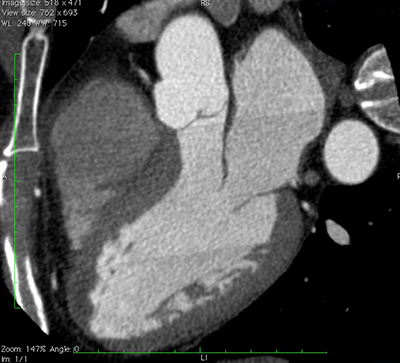

La tomodensitométrie (TDM) cardiaque est une technique d’imagerie qui fait appel à un appareil de radiographie (rayons X); elle fournit des images très détaillées des veines et des artères du cœur. Les images permettent de détecter l’accumulation de plaques ou de calcium dans les vaisseaux sanguins et de repérer de possibles blocages.

L’appareil de tomodensitométrie (tomodensitomètre), que l’on compare parfois à un « beigne », dispose d’une large ouverture dans laquelle s’insère une plateforme (table d’imagerie). Durant l’examen, le patient est allongé sur la table pendant que le tube à rayons X, qui se trouve dans l’anneau de l’appareil, tourne très rapidement autour de lui. Les rayons X traversent le patient sous différents angles avant de frapper les détecteurs de l’appareil qui permettent d’acquérir très rapidement des images transversales détaillées utilisées pour produire des images en trois dimensions (3D) du cœur et de ses vaisseaux sanguins.